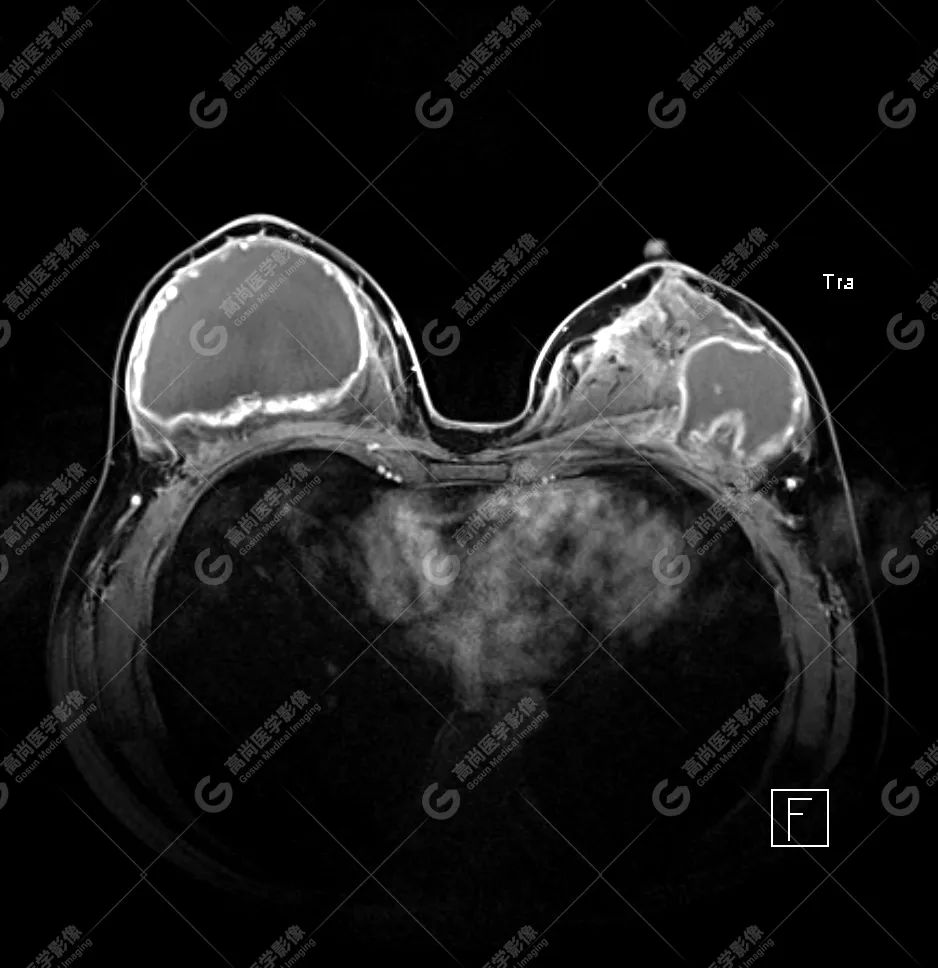

病例 6:乳腺假体植入术后 10 余年,左侧乳腺触及硬结伴疼痛

1、双乳假体包膜完全破裂;左侧腋窝区、胸大肌内、胸大肌与胸小肌间隙、腺体内及双侧假体周围多发注射物渗漏并液化坏死;

2、左侧假体破裂导致的左腋部硅胶相关性淋巴结病,信号复杂。